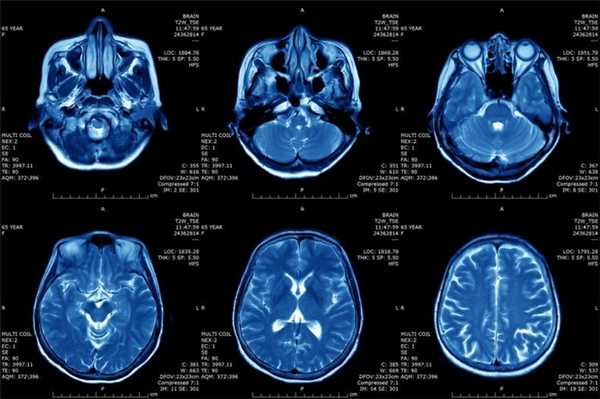

Что показывает МРТ

Магнитно-резонансная томография или МРТ - это сфокусированный метод, который проводит очень детальное обследование. Диагностическая точность МРТ превышает УЗИ и во многих случаях КТ, за исключением сканирования полых органов (легких, желудка, кишечника) и костей. МРТ является золотым стандартом диагностики:

- заболеваний головного и спинного мозга;

- патологий суставов;

- межпозвоночных дисков;

- сердца и сосудов;

- болезней гинекологического, проктологического и урологического характера.

В отличие от быстрого КТ и УЗИ, магнитно-резонансное обследование требует времени - в среднем пациенту нужно лежать в томографе и соблюдать неподвижность 30-60 минут.

Принцип работы МРТ основан на эффекте ядерного магнитного резонанса. МР томограф в своей конструкции имеет мощный магнит, который создает магнитное поле, и датчик, который подает радиочастотные сигналы. В такой ситуации протоны атомов водорода начинают колебательные движения, выделяя при этом импульсы. Их улавливает компьютер томографа и преобразовывает в трехмерные изображения. Чем больше воды содержится в клетках ткани, тем детальней получается ее изображение. Поэтому на МРТ хорошо отображаются органы с большим содержанием воды: МРТ головного мозга, МРТ спинного мозга, МРТ глазных орбит, МРТ органов малого таза, МРТ позвоночника, МРТ суставов, и плохо визуализируются органы с большим содержанием воздуха МРТ органов грудной клетки или кости.

Основы преимуществом МРТ перед КТ и рентгеном является отсутствие в ходе сканирования какого-либо излучения. А вот недостатком этого метода диагностики будет ряд ограничений - наличие ферромагнитного металла в теле пациента и имплантированных в организм водителей ритма, несовместимых с МРТ.

Магнитно-резонансная томография (МРТ)

Принцип МРТ основывается на свойстве ядер атомов реагировать на сильное магнитное поле. Расчёт идёт на реакцию ядер водорода, которых много в составе молекул воды, а тело человека, как известно, на 60% состоит из воды. Попадая в магнитное поле, ядра атомов ориентируются вдоль него, их можно возбуждать и фиксировать энергию, которые они будут отдавать при ослаблении воздействия, т.е. “расслаблении”. Компьютерный анализ позволяет преобразовать полученную информацию и определить расположение, плотность и структуру тканей в организме.

МРТ позволяет “разглядеть” хрящи, мягкие ткани и мозг человека, при этом не оказывая вредного воздействия, поэтому процедуру можно проводить всем и сколько угодно раз. Однако исследование занимает много времени, кроме того, томографы закрытого типа могут вызывать приступы клаустрофобии. Правда, есть аппараты открытого типа. Нельзя проводить процедуру МРТ людям, у которых в тело вживлены электроприборы (например, кардиостимуляторы) или металлические имплантаты.

МРТ будет эффективно при исследовании опухолей, мозга и аномалиях развития сосудов.